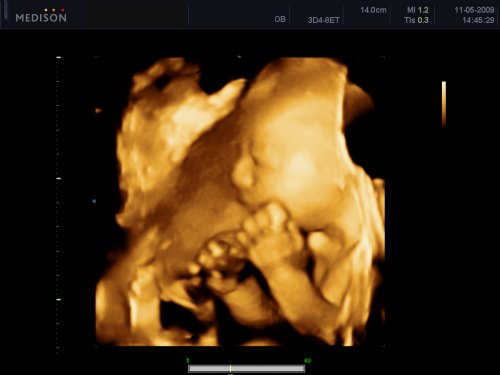

Jupíííí...zítra na 4D ultrazvuk..ten čas tak letí..nedávno jsem zírala na testík a už 4D..se ani neotočím a budu rodit 🙂 Terinka dnes na 4.dávce Prevenaru.. uf uf.. to byl histeráček